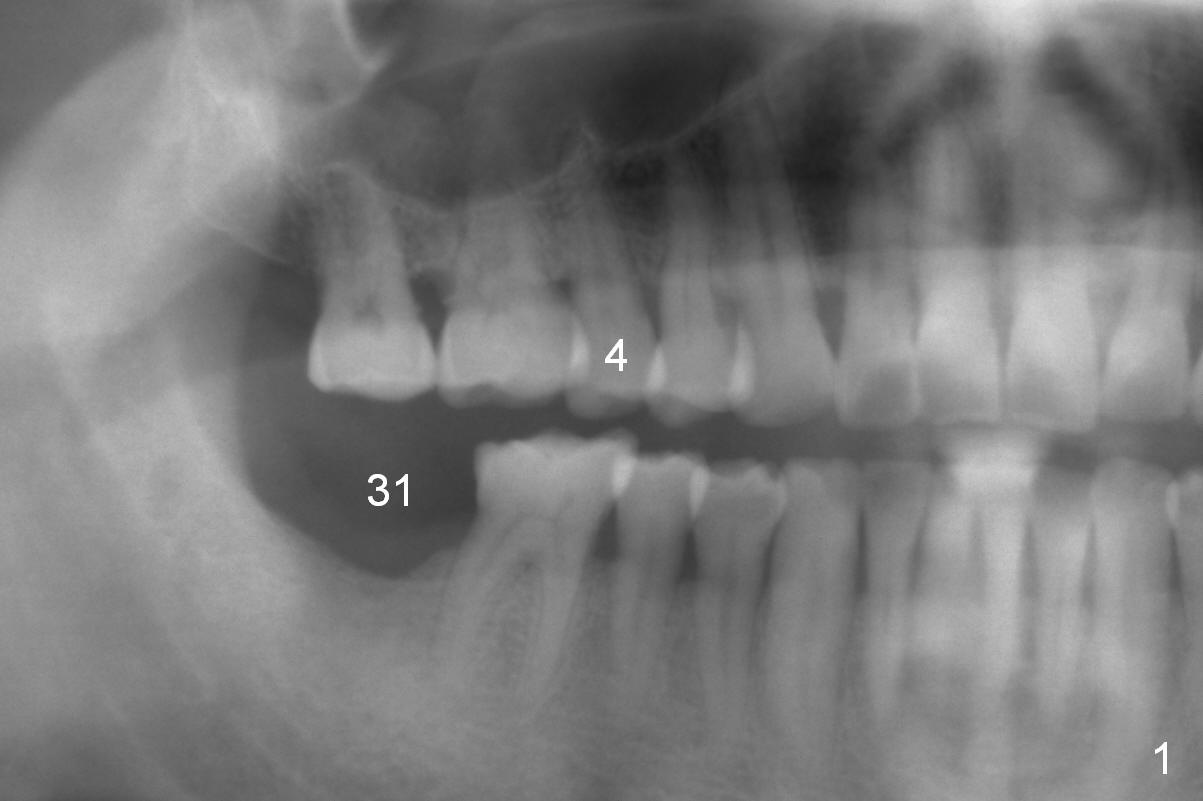

A 61-year-old man (WJ) cracked the tooth #31 after RCT. Four years after #31 extraction, the tooth #4 cracks by itself. The apex of the tooth appears to protrude into the sinus and is closely associated with the sinus septum (triangle: Fig.2,3). An implant will reach the top of the socket for stability (Fig.4 black area). The abutment is expected to be 4.8x4(3) (SM) or 4.5x4(3) (UF) mm. Metronidazole will be used for disinfection of the socket. On returning, he requests #31 implant.